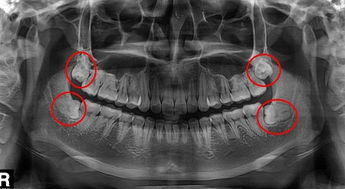

1、口腔全景片怎麽(me) 看有沒有智齒

比如下圖這張全景片,全口牙齒一般有28-32顆多出來的4顆就是智齒,智齒是從(cong) 中間的牙齒往後數的第8顆,如果上下左右都有第8顆,那就是長了4顆智齒。